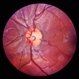

- Vascular Loops

- vascular loop

- Color photo showing corkscrew loop on right optic nerve.